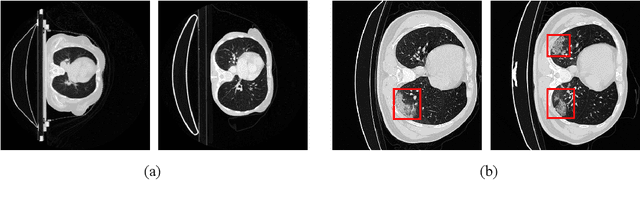

Abstract:Class imbalance has been one of the major challenges for medical image segmentation. The model cascade (MC) strategy significantly alleviates class imbalance issue. In spite of its outstanding performance, this method leads to an undesired system complexity and meanwhile ignores the relevance among the models. To handle these flaws of MC, we propose in this paper a light-weight deep model, i.e., the One-pass Multi-task Network (OM-Net) to solve class imbalance better than MC and require only one-pass computation for brain tumor segmentation. First, OM-Net integrates the separate segmentation tasks into one deep model. Second, to optimize OM-Net more effectively, we take advantage of the correlation among tasks to design an online training data transfer strategy and a curriculum learning-based training strategy. Third, we further propose to share prediction results between tasks, which enables us to design a cross-task guided attention (CGA) module. With the guidance of prediction results provided by the previous task, CGA can adaptively recalibrate channel-wise feature responses based on the category-specific statistics. Finally, a simple yet effective post-processing method is introduced to refine the segmentation results of the proposed attention network. Extensive experiments are performed to justify the effectiveness of the proposed techniques. Most impressively, we achieve state-of-the-art performance on the BraTS 2015 and BraTS 2017 datasets. With the proposed approaches, we also won the joint third place in the BraTS 2018 challenge among 64 participating teams. We will make the code publicly available at https://github.com/chenhong-zhou/OM-Net.